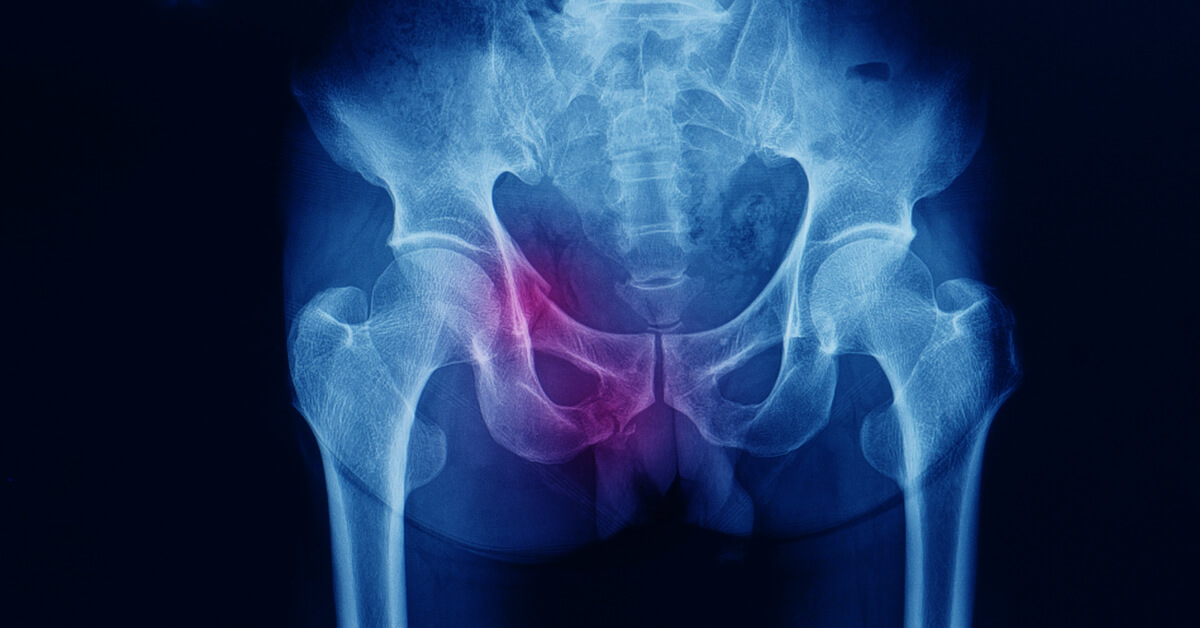

يتم تشخيص الكسر عادة باستخدام تصوير الأشعة السينية للحوض لتحديد تفاصيل الكسر بدقة، يطلب من الطبيب إجراء فحص بالأشعة المقطعية، حيث يجري الدكتور عمرو أمل أفضل دكتور عظام في مصر تقييم شامل للأعضاء الداخلية والأوعية الدموية والأعصاب المحيطة للتأكد من عدم وجود إصابات إضافية مرتبطة بالكسر.

علاج شرخ مفصل الحوض يتم تحديده وفقاً لمدى شدة الإصابة التي قد تعرض لها الفرد وعمره، حيث يقوم الطبيب المتخصص في البداية بتشخيص الحالة جيداً من خلال طلب صور إشاعات واضحة تبين العظام بطريقة واضحة مدى الضرر الواقع عليها، وبعد ذلك يبدأ في تطبيق العلاج المناسب للمريض وينصحه بالراحة طوال فترة العلاج وتجنب القيام بأي حركة خاطئة مع اتباع برنامج علاج طبيعي يسرع من عملية الشفاء.